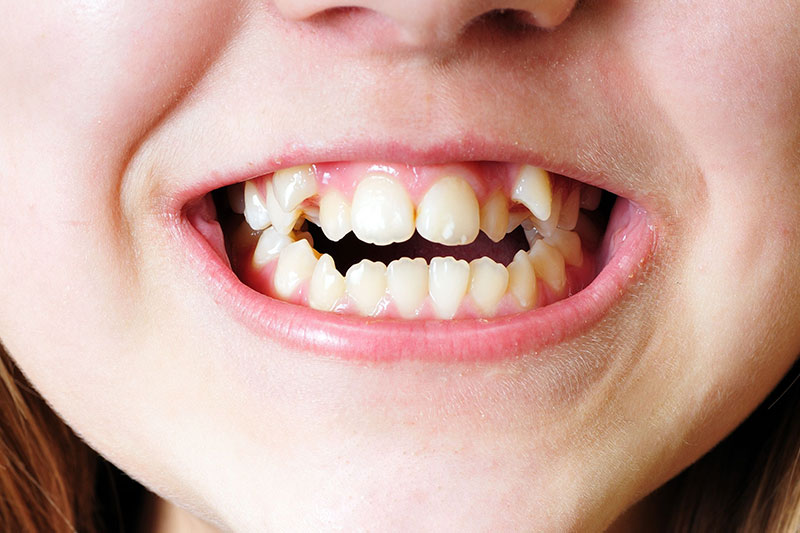

治療前

| 主訴 | 歯並びの乱れを改善したい |